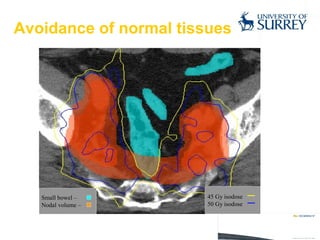

Avoidance of normal tissues

• #20 IMRT is a new radiotherapy technique able to treat complex volumes and to specifically reduce the irradiation of sensitive normal structures. CLICK This patient has prostate cancer with a high risk of nodal metastases, but the radiation dose that can be delivered to those nodes is limited to 50 Gy by presence of small bowel, as can be seen. CLICK,CLICK, CLICK Standard radiotherapy would involve irradiating the larger volume to 50 Gy, and boosting the prostate to a further 20 Gy. CLICK IMRT is able to deliver a variable dose per fraction, and this can be used for selective normal tissue avoidance – in this case bowel, or to deliver a higher dose to part of the tumour, in this case we have treated the prostate to a higher dose than the pelvic nodes.